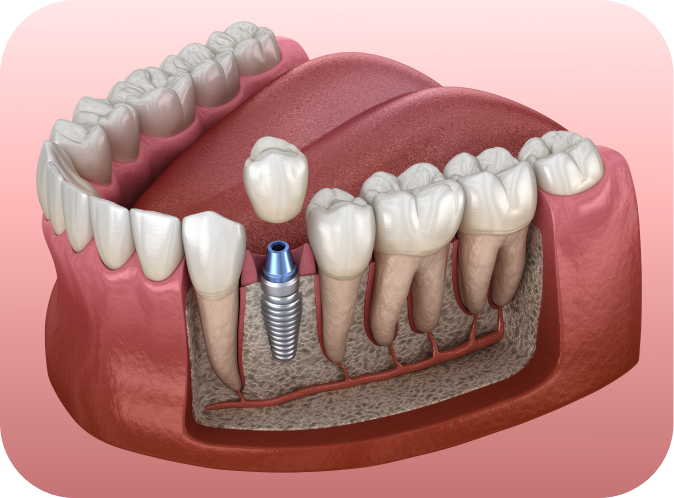

L’implant est une vis en titane insérée dans l’os de la mâchoire. Il remplace la racine d’une dent absente. Ensuite, le praticien fixe une couronne ou une prothèse sur cet implant. Ainsi, le patient retrouve une fonction masticatoire et un confort quotidien.

Grâce à un phénomène biologique appelé ostéo-intégration, l’os entoure progressivement l’implant. Cependant, ce processus ne fonctionne que si l’environnement est sain. La présence de bactéries ou d’inflammations peut perturber cette phase cruciale. C’est pourquoi il faut assainir la bouche avant tout acte chirurgical.